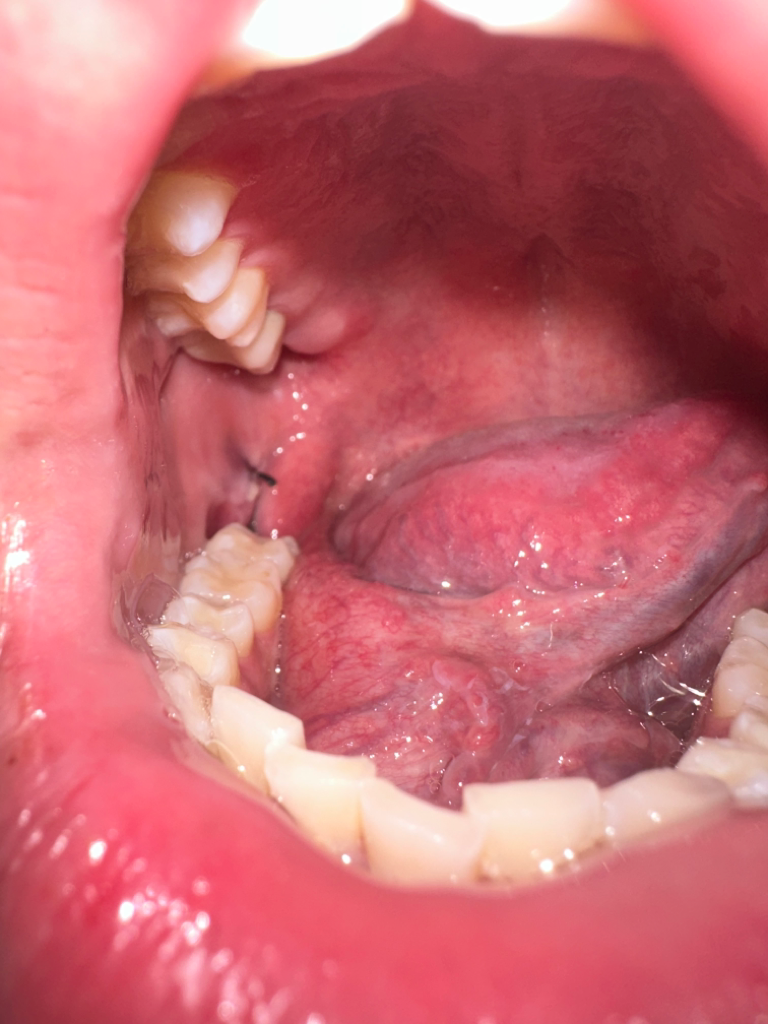

상피세포가 차오르면서 하얗게 나타납니다. 잘 낫고 있으니 실밥 풀고 오시면 되겠습니다.

원래 사랑니 뽑은 부위 주위 가장자리 잇몸은 흰색으로 보이며 이것은 정상적인 치유과정이니 그냥두면 됩니다.

사진 상으로는 정상적인 치유 과정으로 보이며, 통증이나 붓기가 심한 경우가 아니라면 크게 걱정 안하셔도 괜찮습니다

조직이 치유가 되면서 차오르게 되면 하얀색으로 보이는 경우도 있습니다.

사진으로만 봤을 경우에는 큰 문제가 없는것으로 보여요.